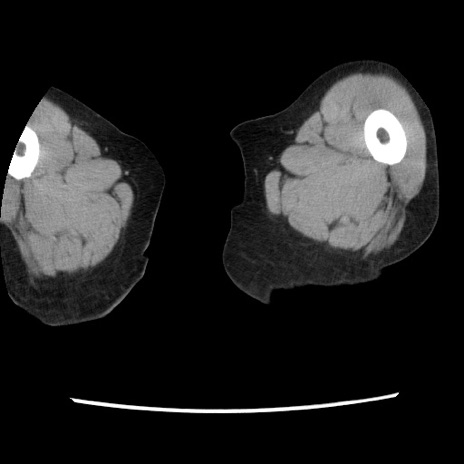

【症例】80歳代女性

【主訴】腹痛

【現病歴】8時間前から腹痛あり来院。

【既往歴】糖尿病、脂質異常症、子宮体癌にて子宮全摘術

【身体所見】意識清明・会話良好だが腹痛で苦悶様、全腹部にわたって反跳痛と圧痛あり

【データ】WBC 13600、CRP 0.14、LDH 224、CK 90